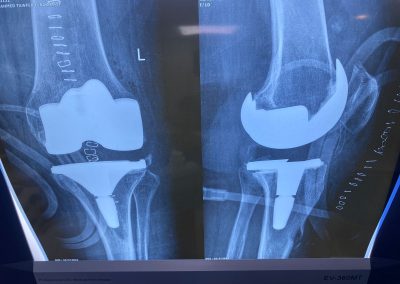

السيده/ عزه الرخاوي العمر ٦٨ عام كانت تعاني من تآكل شديد بالركبتين تم تغيير المفصل الايسر منذ ٣ أعوام تم تغيير المفصل الايمن منذ ٨ اشهر هي الآن تمشي بشكل طبيعي تماما